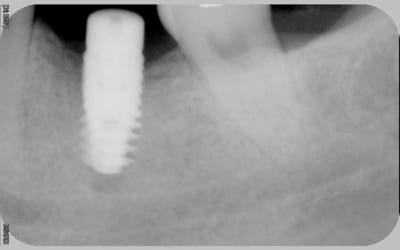

Il manque les radios du jour de la pose, j'ai l'impression que les implants ne sont pas assez enfouis . Pa exemple Anthogyr recommande de poser l'Axiom 0.5mm en sous crestal, que préconise Tekka ?

En ce qui concerne la radio de la 21 , on dirait qu'il a été mis dans un site d'extraction et qu'il n'est pas assez large.

Tekka préconise un enfouissement à 1 voir 1,5mm sous crestal pour l'in-kone. Pour le krestal je sais pas, vue que c'est pas la même connectique.